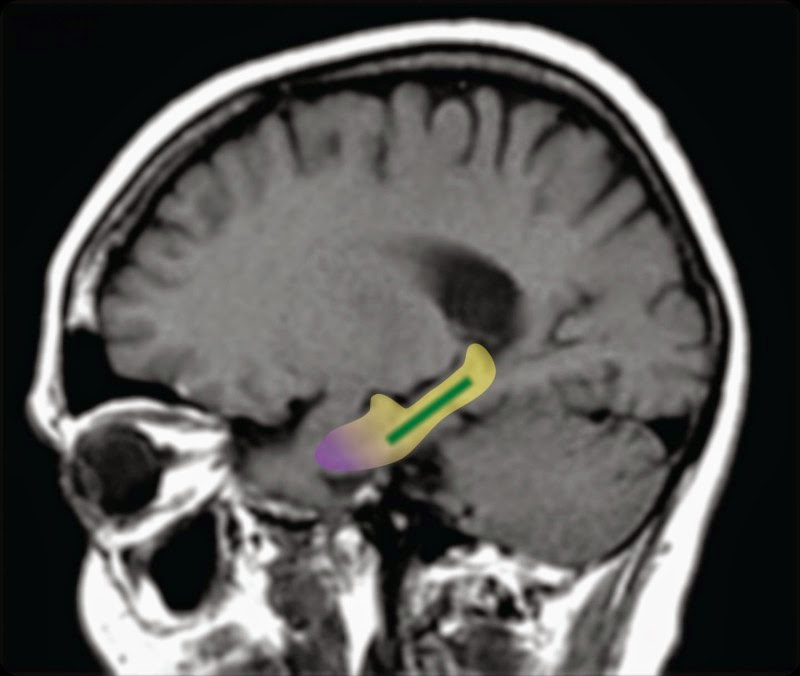

El hipocampo es la estructura del cerebro donde se consolida la memoria y es el responsable de almacenar y manejar los recuerdos y toda la información que vamos adquiriendo en la vida. El giro dentado se altera como parte del proceso natural de envejecimiento cerebral produciendo como consecuencia disminución de la memoria, pero no tiene nada que ver con otra región vecina del hipocampo, la corteza entorrinal, esa sí involucrada en la enfermedad de Alzheimer.

Trabajos anteriores que conectaban una región específica del cerebro al deterioro en la memoria –el giro dentado– establecían sólo una correlación, no una causa directa. Para probar si es una causa, los investigadores de la Universidad de Columbia usaron los flavonoides del cacao para saber si su consumo mejoraba el funcionamiento del giro dentado y disminuía el daño en la memoria.

En el estudio, 37 voluntarios en buen estado de salud, con edades entre 50 y 69 años, fueron asignados al azar a un grupo que tomaba una bebida con un alto contenido de flavonoides (900mg al día) y a otro que la consumía con bajo contenido (10mg), durante 3 meses. Análisis de imágenes cerebrales y pruebas de memoria se realizaron antes y después del estudio. Las imágenes cerebrales medían el volumen de sangre en el giro dentado (una medida del metabolismo) y la prueba de memoria consistía en una específica, de 20 minutos, diseñada para evaluar el estado de esa región del hipocampo.

“Cuando observamos las imágenes del cerebro de nuestros sujetos de estudio, encontramos una mejoría notable en la función del giro dentado (verde en la imagen) en aquellos individuos que consumieron los niveles más altos de flavonoides”, dice Adam M. Brickman, investigador principal y profesor de neuro psicología.